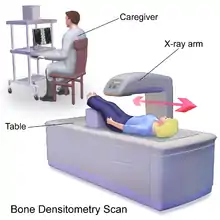

Dual-energy X-ray absorptiometry (DXA, or DEXA[1]) is a means of measuring bone mineral density (BMD) using spectral imaging. Two X-ray beams, with different energy levels, are aimed at the patient's bones. When soft tissue absorption is subtracted out, the bone mineral density (BMD) can be determined from the absorption of each beam by bone. Dual-energy X-ray absorptiometry is the most widely used and most thoroughly studied bone density measurement technology.

The DXA scan is typically used to diagnose and follow osteoporosis, as contrasted to the nuclear bone scan, which is sensitive to certain metabolic diseases of bones in which bones are attempting to heal from infections, fractures, or tumors. It is also sometimes used to assess body composition.